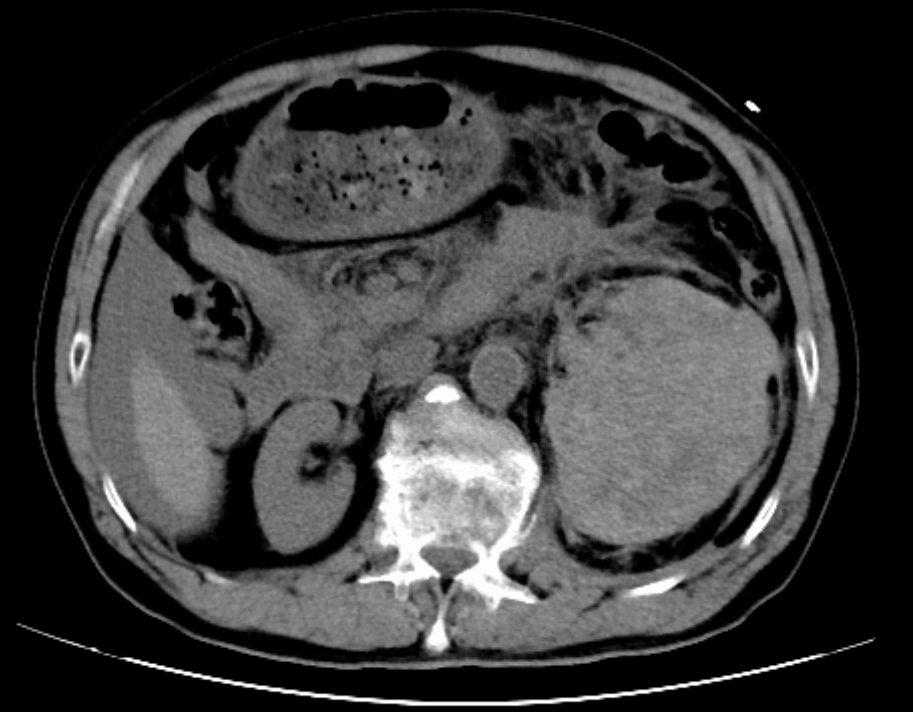

创伤中心肝胆胃肠外科医师为患者行腹腔诊断性穿刺,抽出不凝血,结合CT影像结果,确诊患者为腹腔脏器多发伤,具备急诊开腹手术指征。但患者此时仍处于休克状态,手术实施难度大、风险高。经医务部快速协调,急诊重症监护病房、肝胆胃肠外科、泌尿外科、麻醉科、输血科、放射科等相关科室专家迅速集结,开展紧急会诊。

在急诊重症监护病房团队的精准复苏下,患者生命体征暂时趋于稳定,随即被送往手术室。肝胆外科、泌尿外科、结直肠外科手术团队联合开展急诊开腹手术,术中发现患者存在肾裂伤、脾裂伤、肠系膜血肿,腹腔内积血已达2500ml,约占人体全身血液量的50%。手术团队沉着规范操作,快速定位出血点并实施止血,因患者左肾中下极碎裂,基本横断分离,局部缝合止血效果差,经团队充分讨论后,决定为患者行左肾切除术,手术顺利完成,成功止住致命大出血。